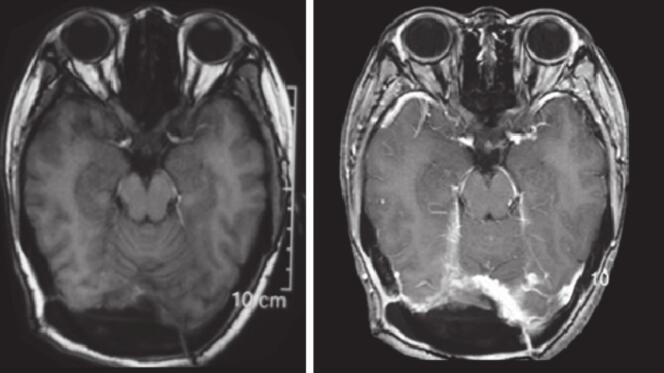

图2 术前头颅MRI和MRV检查图像

MRI提示窦汇区占位,T1、T2、DWI均表现为混杂信号,增强后可见明显不均匀强化,未见明显“脑膜拖尾征”。MRV提示窦汇不能显示,上矢状窦下端和两侧横窦均受压,部分显影